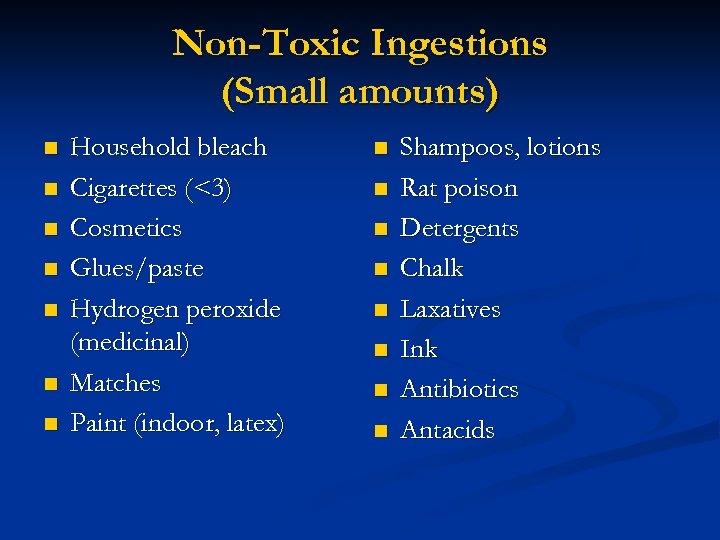

Non-Toxic Ingestions (Small amounts) n n n n Household bleach Cigarettes (<3) Cosmetics Glues/paste Hydrogen peroxide (medicinal) Matches Paint (indoor, latex) n n n n Shampoos, lotions Rat poison Detergents Chalk Laxatives Ink Antibiotics Antacids

Non-Toxic Ingestions (Small amounts) n n n n Household bleach Cigarettes (<3) Cosmetics Glues/paste Hydrogen peroxide (medicinal) Matches Paint (indoor, latex) n n n n Shampoos, lotions Rat poison Detergents Chalk Laxatives Ink Antibiotics Antacids